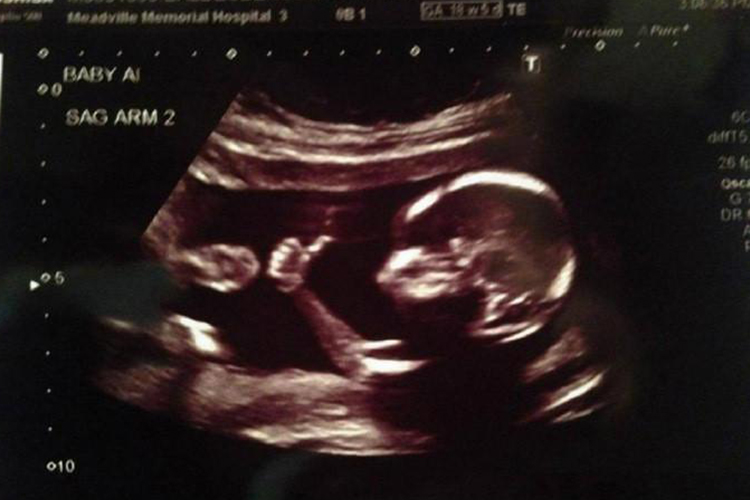

18周的胎儿生长大约有14厘米,体重约150克,面部轮廓发育更明显。

18周的胎儿生长大约有14厘米,体重约150克,头皮已长毛发。胎儿此时胸脯会一鼓一鼓的,这是在呼吸,但这时的胎儿吸入呼出的不是空气而是羊水。

在这一周,原来偏向两侧的眼睛开始向前集中。面部发育得更明显,开始有最早的面部表情,还能皱眉、斜眼、做鬼脸。因胎儿此时的皮肤是半透明的,可以清楚看见皮下血管,也能够看见全身开始长硬的骨骼。